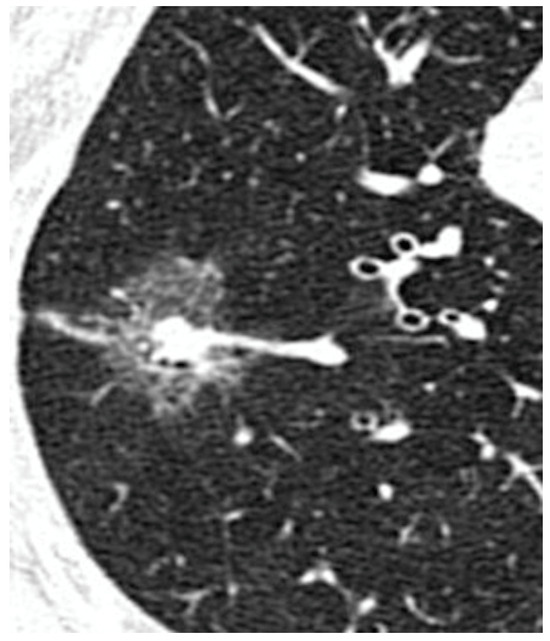

Prognostic Factors of Non-Predominant-Lepidic Lung Adenocarcinoma Presenting as Ground Glass Opacity: Results of a Multicenter Study

| Pure GGO, n (%) | 162 (42%) | 108 (67%) | 54 (24%) | <0.0001 |

| Pure GGO | 3.3 | 2.9–4.5 | 0.01 |

| Pure GGO | 2.3 | 2.8–4.8 | 0.003 |